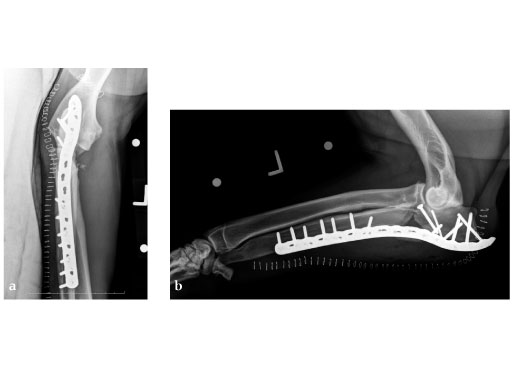

5-year-old male English Mastiff, road traffic accident.

(Case provided by Michael P Kowaleski, North Grafton, USA)